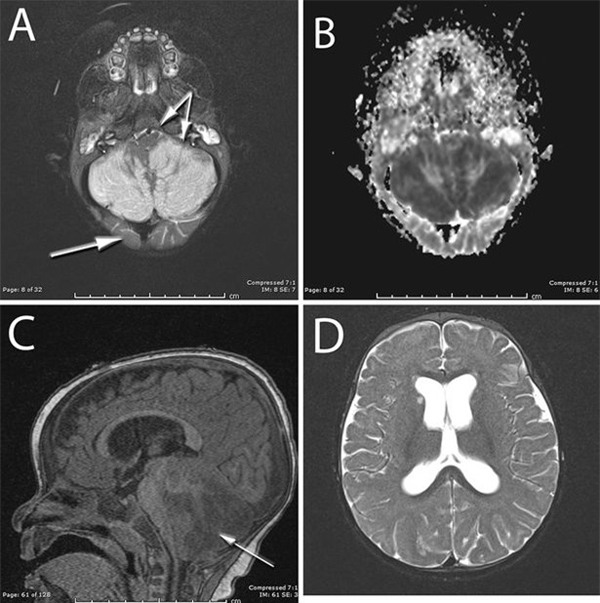

Kết quả chụp não bộ của bé gái.

Khi nhập viện, bé gái trong tình trạng rất nặng, các bác sĩ phải dùng tới máy trợ thở, đặt ống nội khí quản và cấp cứu. Kết quả chụp phim xác định bé bị tổn thương phần dưới cùng của não bộ và ngăn chặn dịch não tủy di chuyển có thể dẫn đến hôn mê và tử vong. Các bác sĩ đã tiến hành phẫu thuật khẩn cấp cắt bớt xương sọ để giảm bớt tình trạng sưng lên của não.